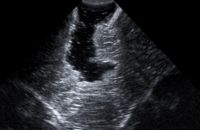

Hochauflösender Intraoperativer Ultraschall

Der intraoperative Ultraschall ermöglicht es, anatomische und pathologische Strukturen während der Operation mittels Schallwellen bildlich darzustellen. Ein entscheidender Vorteil dieser Methode ist die hohe Mobilität des Ultraschallgeräts, das aufgrund seiner kompakten Größe jederzeit ohne umfangreiche Vorbereitung und ohne zusätzliche Kosten eingesetzt werden kann. Allerdings gibt es auch einige Einschränkungen, wie die begrenzte räumliche Darstellung, die Herausforderung bei der Handhabung bei sehr kleinen Zugangswegen sowie die Variabilität der Untersuchergebnisse je nach Erfahrung des Bedienpersonals. Der Ultraschall stellt eine äußerst wertvolle komplementäre Methode zur intraoperativen Visualisierung dar und wird in der Praxis regelmäßig genutzt. Die Neurochirurgie Tübingen verfügt über drei hochauflösende Ultraschallgeräte, darunter das moderne BK 5000 der Firma BK Medical. Die Geräte sind in die Navigationsinfrastruktur der digitalen Operationssäle integriert.